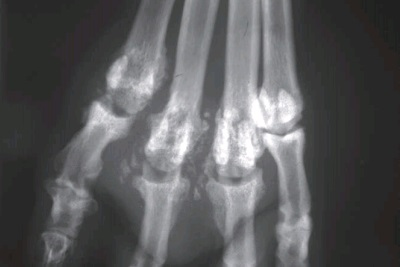

Фото 3. Актиномикоз собак и кошек. Выраженная отечность с эритемой и свищевым каналом на лапе взрослой собаки. Обратите внимание ,что участки кожи и подкожной клетчатки были взяты для гистопатологии и получения культуры (бактериальной и грибковой).

Фото 4. Актиномикоз собак и кошек. Та же собака с фото 3. Рентгенография пальцев лапы продемонстрировала наличие костных изменений, характерных для целлюлита и остеомиелита.